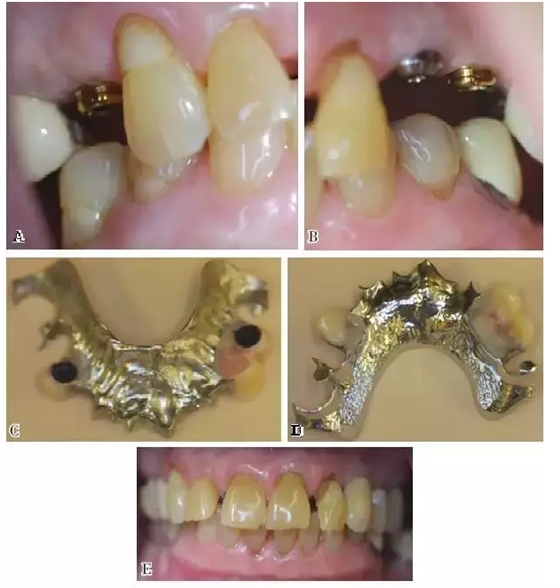

圖5:KennedyⅢ類缺損。3號(hào)牙位的種植體和天然牙的舌隆突及近中牙合支托提供了支持力,5號(hào)和12號(hào)牙位的種植體提供固位力。導(dǎo)平面增強(qiáng)了種植體的固位力,因而不再需要卡環(huán)